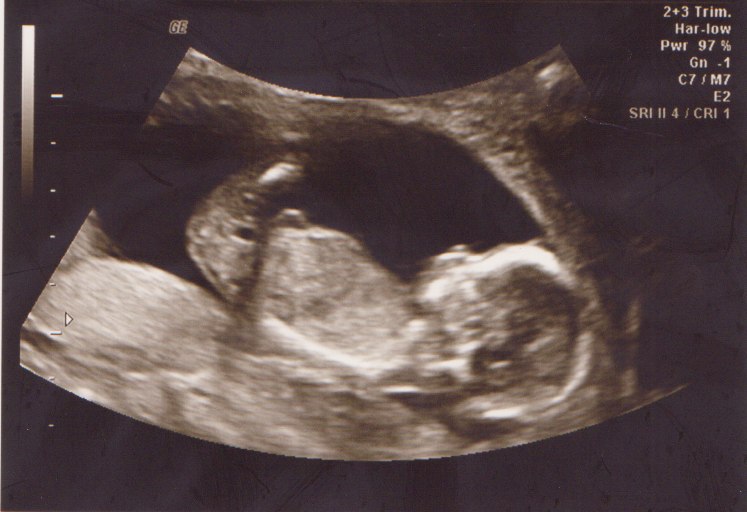

Sikke en fantastisk oplevelse vi havde

Hun fik hurtigt spottet det var en lille prinsesse, og hun sagde, hun lå så fint, at vi næsten lige skulle se hende i 3D også, og alt var bare helt perfekt

Hun sagde det var en rigtig lille model med laaange ben... Så nu er farmand ved at undersøge hvad jagttegn koster  Haha...

Vedhæftede fotos (klik for at se i fuld størrelse)